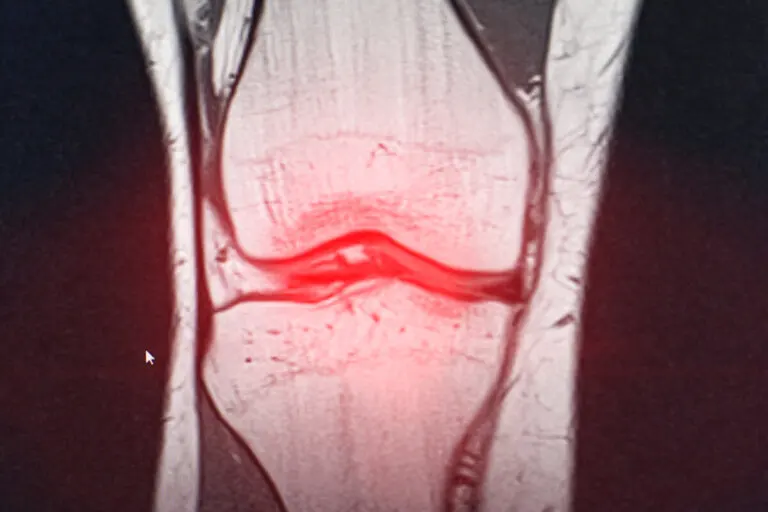

- Resonancia magnética.